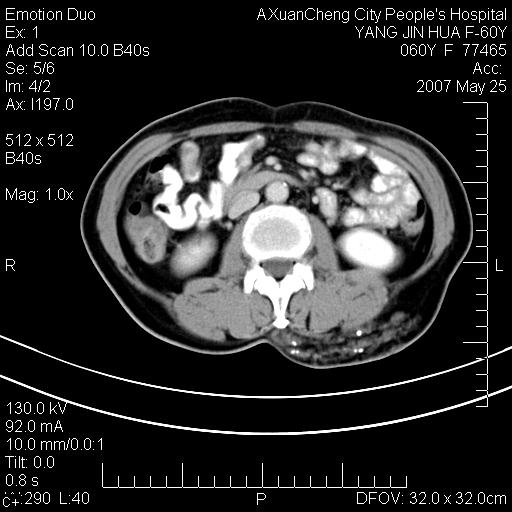

发现左侧腰背部包块40余年,逐渐长大,质软,局部表面可见扩张的血管影

左背部皮下良性肿瘤,密度不均,边界不清,内有脂肪、钙化,增强扫描无明显强化,血管平滑肌脂肪瘤?进一步诊断有困难,建议穿刺活检。

左侧背部皮下混杂密度肿块,结构较疏松,边缘欠光整,内有多发斑点状钙化,考虑:皮下血管瘤。

这个病理增强扫描之前,我们是考虑是血管瘤,可是现在增强后一点强化都没有,还能考虑是血管瘤吗